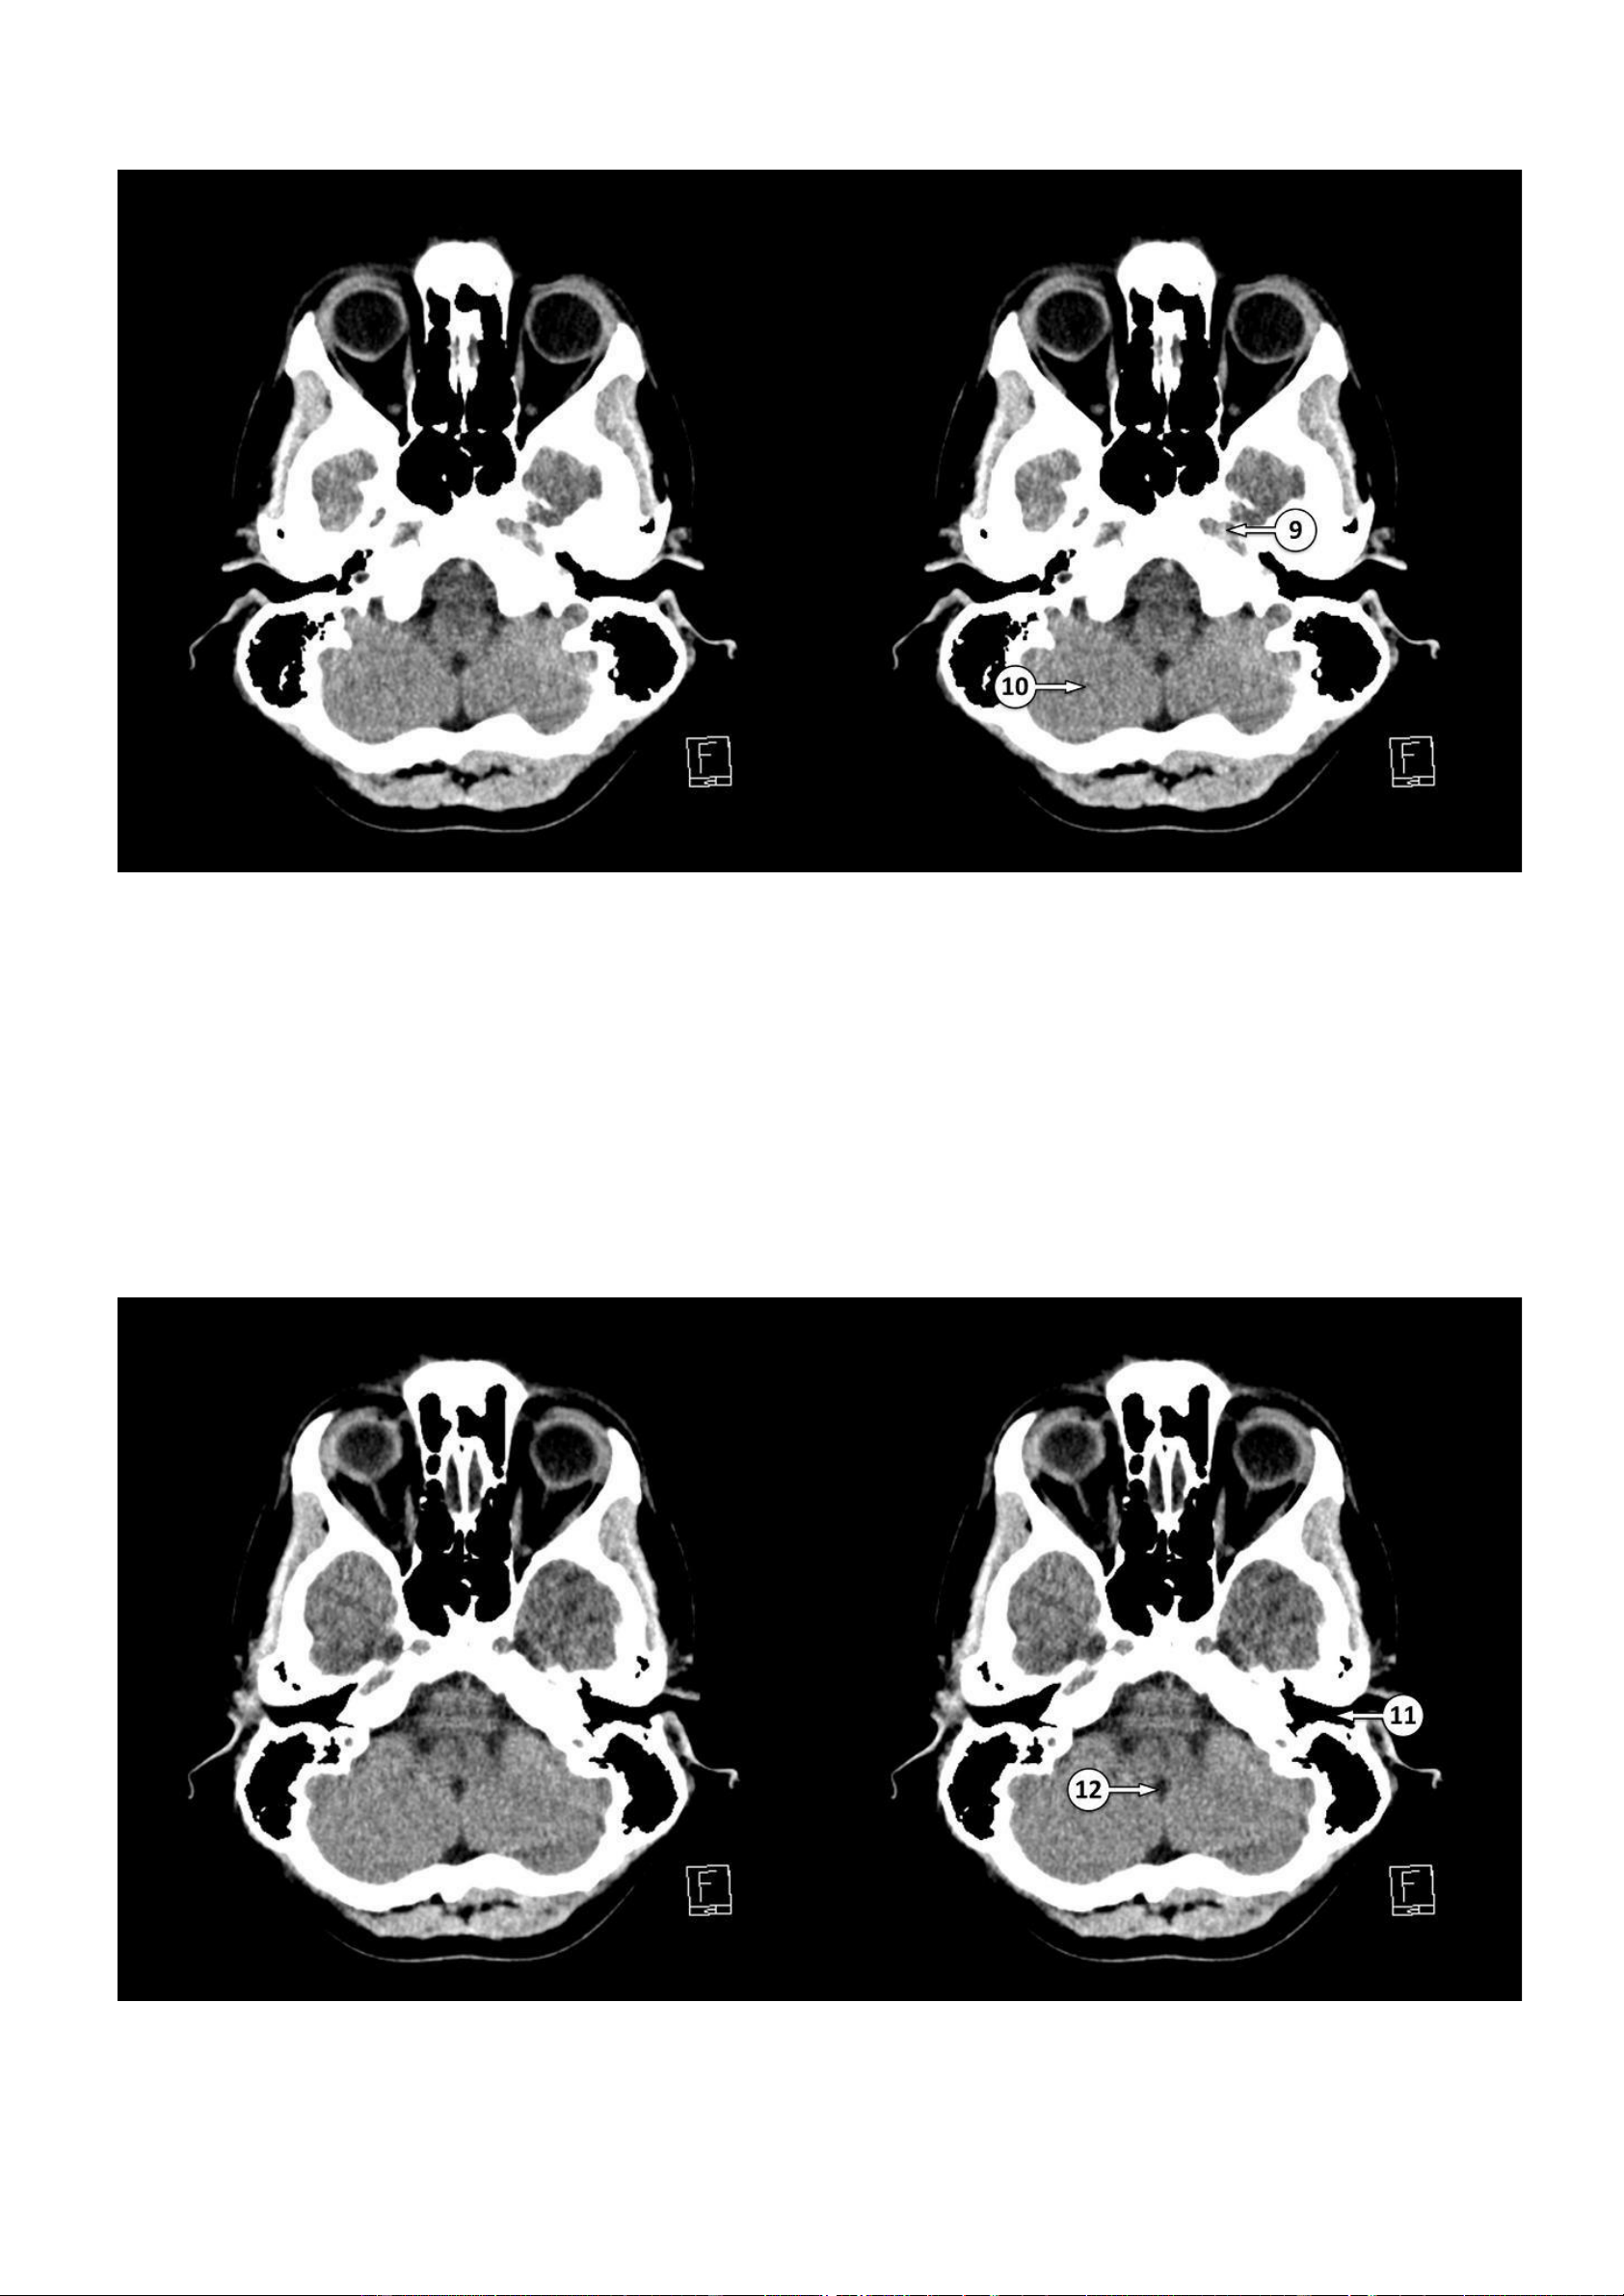

▪ Số 9: Động mạch cảnh trong đoạn trong xương đá nằm trong ống động mạch cảnh

▪ Số 10: Bán cầu tiểu não 11: Ống tai ngoài 12: Lỗ Magendie lOMoAR cPSD| 22014077